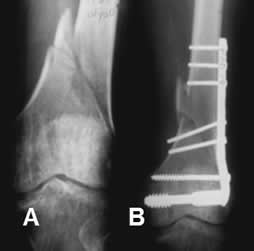

Fig 99. Tornillos de esponjosa y de cortical.

Rx AP. Fractura bimaleolar. La del medial está fijada con tornillos de esponjosa y la del lateral, con placa y tornillos de cortical.